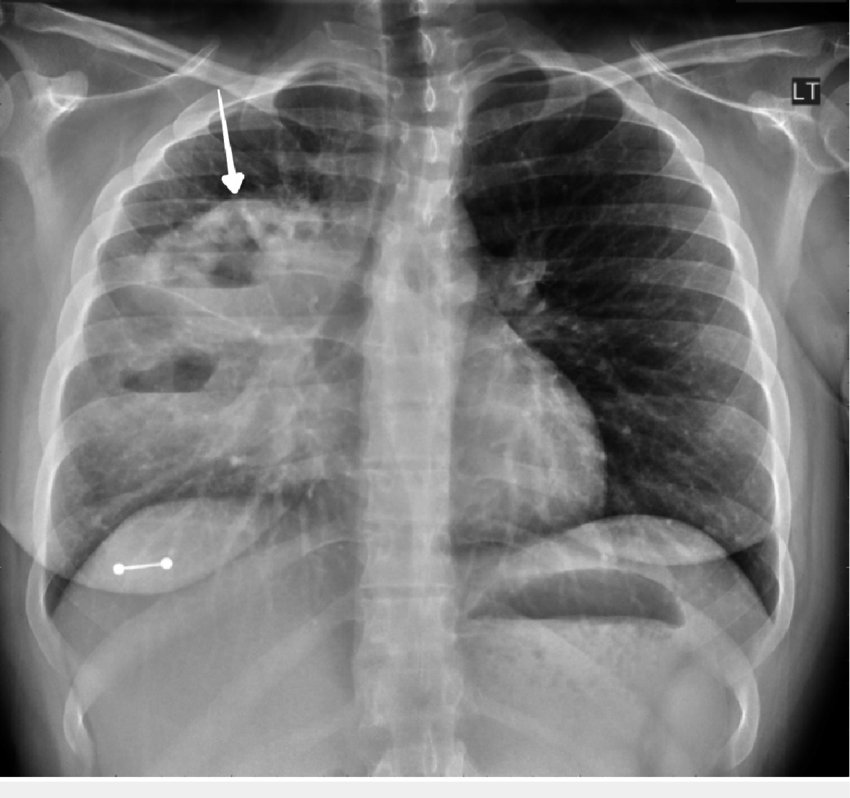

Dr sthanu subramanian@drsthanus·

A female in her 20s, an active smoker, with no significant past medical hx, presented with a worsening productive cough, night sweats, and a 20-pound weight loss over six months. Thoughts?